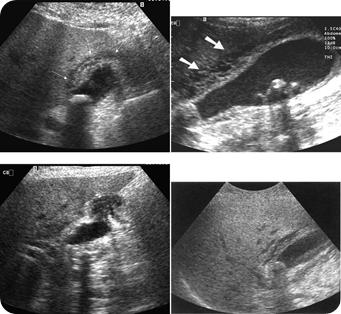

Acute cholecystitis: (a) TS of an oedematous, thickened gallbladder wall with a stone. (b) LS with a

thickened wall (arrows). Stones and debris are present. (c) and (d) TS and LS demonstrating pericholecystic fluid.